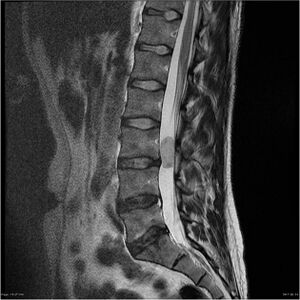

Extramedullary tumors represent the majority of intradural tumors, the vast majority being benign CNS neoplasias. The primary treatment is in most cases surgical, according to the individual dispositions of the patient there is the possibility of applying radiotherapy or chemotherapy. All symptomatology associated with these tumors is dependent on the location and size of the neoplasia, primarily spinal cord or cauda compression and related symptoms. [4] náhled|MRI – spinální meningeom